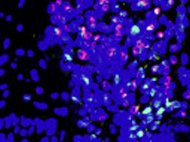

Dendritic Cells are “tree-shaped” Bone-marrow derived Leukocytes responsible for initiation of adaptive immune responses. They are the most potent antigen-presenting cells. Since they induce T Cell activation research...